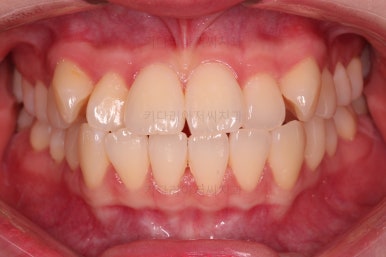

교합이 안정되었고, 치열도 가지런해졌으며 앞니 각도나 덧니 부분도 상당히 좋아졌어요.

부산교정전문의 전후 사진을 비교해 볼게요.

발치교정치고는 비교적 짧은 기간인 20개월만에 치열, 교합, 뻗친 느낌, 원하는 만큼의 입매 등 많은 점이 잘 개선된 치료였습니다.